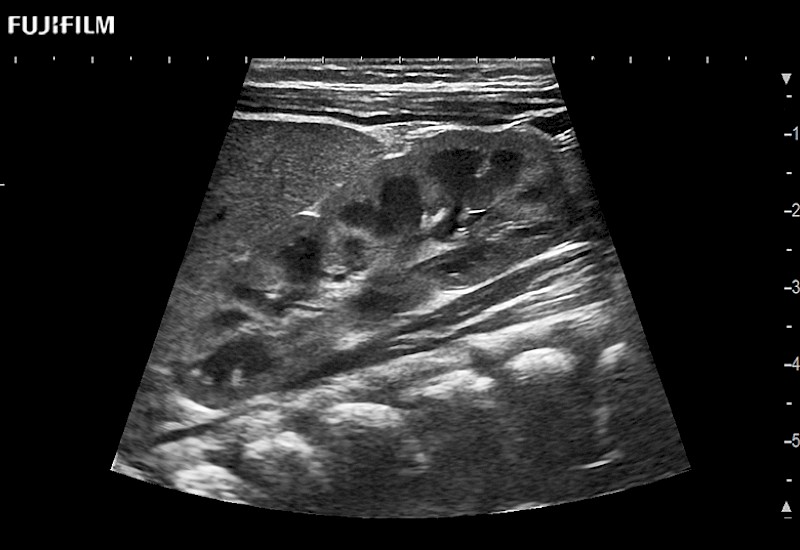

Fujifilm Healthcare understands that Surgical Oncologists demand excellence in their operating rooms — from their staff and the equipment they depend on. Fujifilm Healthcare's dedication to Surgical Oncologists provides outstanding ultrasound technology, professional support and the specialized tools necessary to best perform comprehensive real-time ultrasound imaging.

For precise surgical oncology ultrasound imaging, Fujifilm Healthcare offers premium level solutions that include:

for use during open and laparoscopic procedures: Tumor localization & staging, Ablation, Resection, Biopsy, Transplant, Abdominal exploration, Robotic surgery